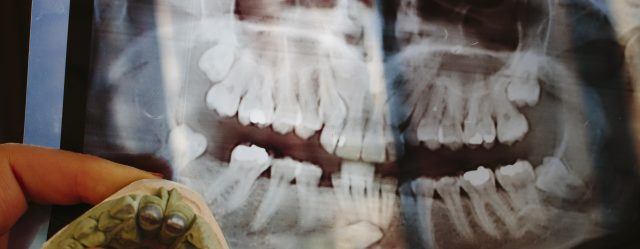

顎骨X線検査

う蝕の存在や歯周病、顎骨内病変などのスクリーニングを行う。

オルソパントモ